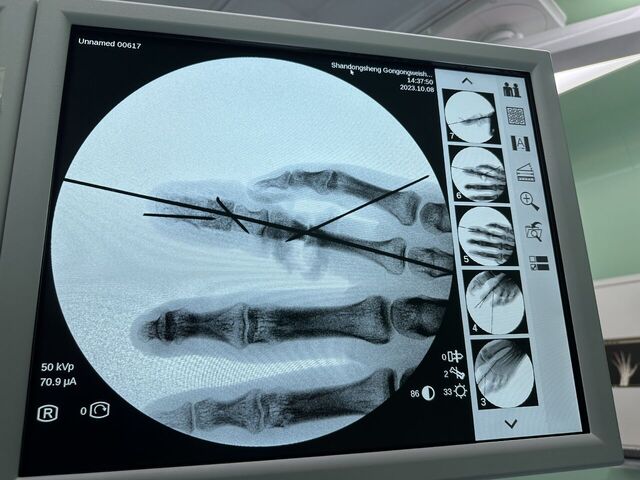

拇指再造术后一年半随访